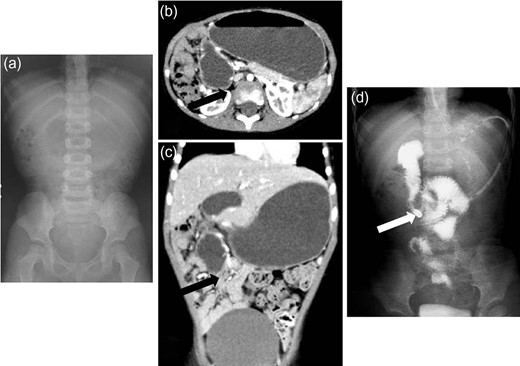

A 3-year-old boy was admitted with bilious vomiting. Abdominal X-ray films showed a gasless abdomen (Fig. 3a). Enhanced CT findings were consistent with duodenal obstruction (Fig. 3b and c). A barium meal revealed malrotation and it was difficult to insert an enteral feeding tube into the small intestine (Fig. 3d). He underwent a laparotomy, and the intra-operative findings revealed Ladd’s bands associated with mesenterium ileocolicum commune and malrotation of the intestine (Fig. 4a and b). He underwent division of the abnormal bands tethering the duodenum, which caused extrinsic compression, widening of the mesenteric base to prevent a further volvulus, and an appendectomy. He is currently doing well without a recurrence.

Radiologic findings from Case 2. (a) Abdominal X-ray films showing a gasless abdomen. (b and c) Enhanced CT showing a suspected duodenal obstruction (black arrow: suspected lesion). (d) Barium meal revealing malrotation and difficulty inserting the enteral feeding tube into the small intestine (white arrow: the tip of the tube).